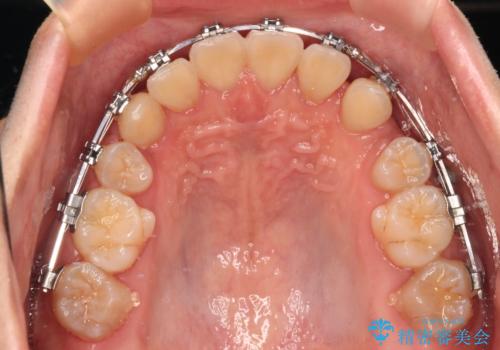

- 矯正装置

- メタルブラケット

- 前歯のデコボコや八重歯を気にして来院された患者様です。

左右ともに奥歯の咬み合わせに問題があり、上顎臼歯が前方位にある状態で、結果として上顎前歯全体が前方位かつ叢生になっていました。

また、左右ともに上顎最後臼歯が頬側に転移していたため、補助装置を用いて舌側に移動をさせながら、上顎前歯を引っ込むように移動させることとしました。

口元の突出感を解消させるため上顎左右第一小臼歯2本を抜歯して、ワイヤー装置にて矯正治療を行うこととしました。